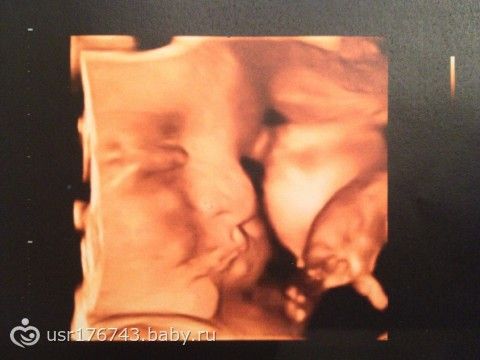

На прошлой неделе ходили на узи, наш любимый мужчина Михаил весит 1545 г, рост — 39 см, лежит головкой правильно вниз, и толкает мамку в правое ребро стопочками длинной 6 см!

(фоточки маси прилагаются).

У нас всё хорошо, никаких обвитий, и допплер тоже отличный, чему мы очень рады.